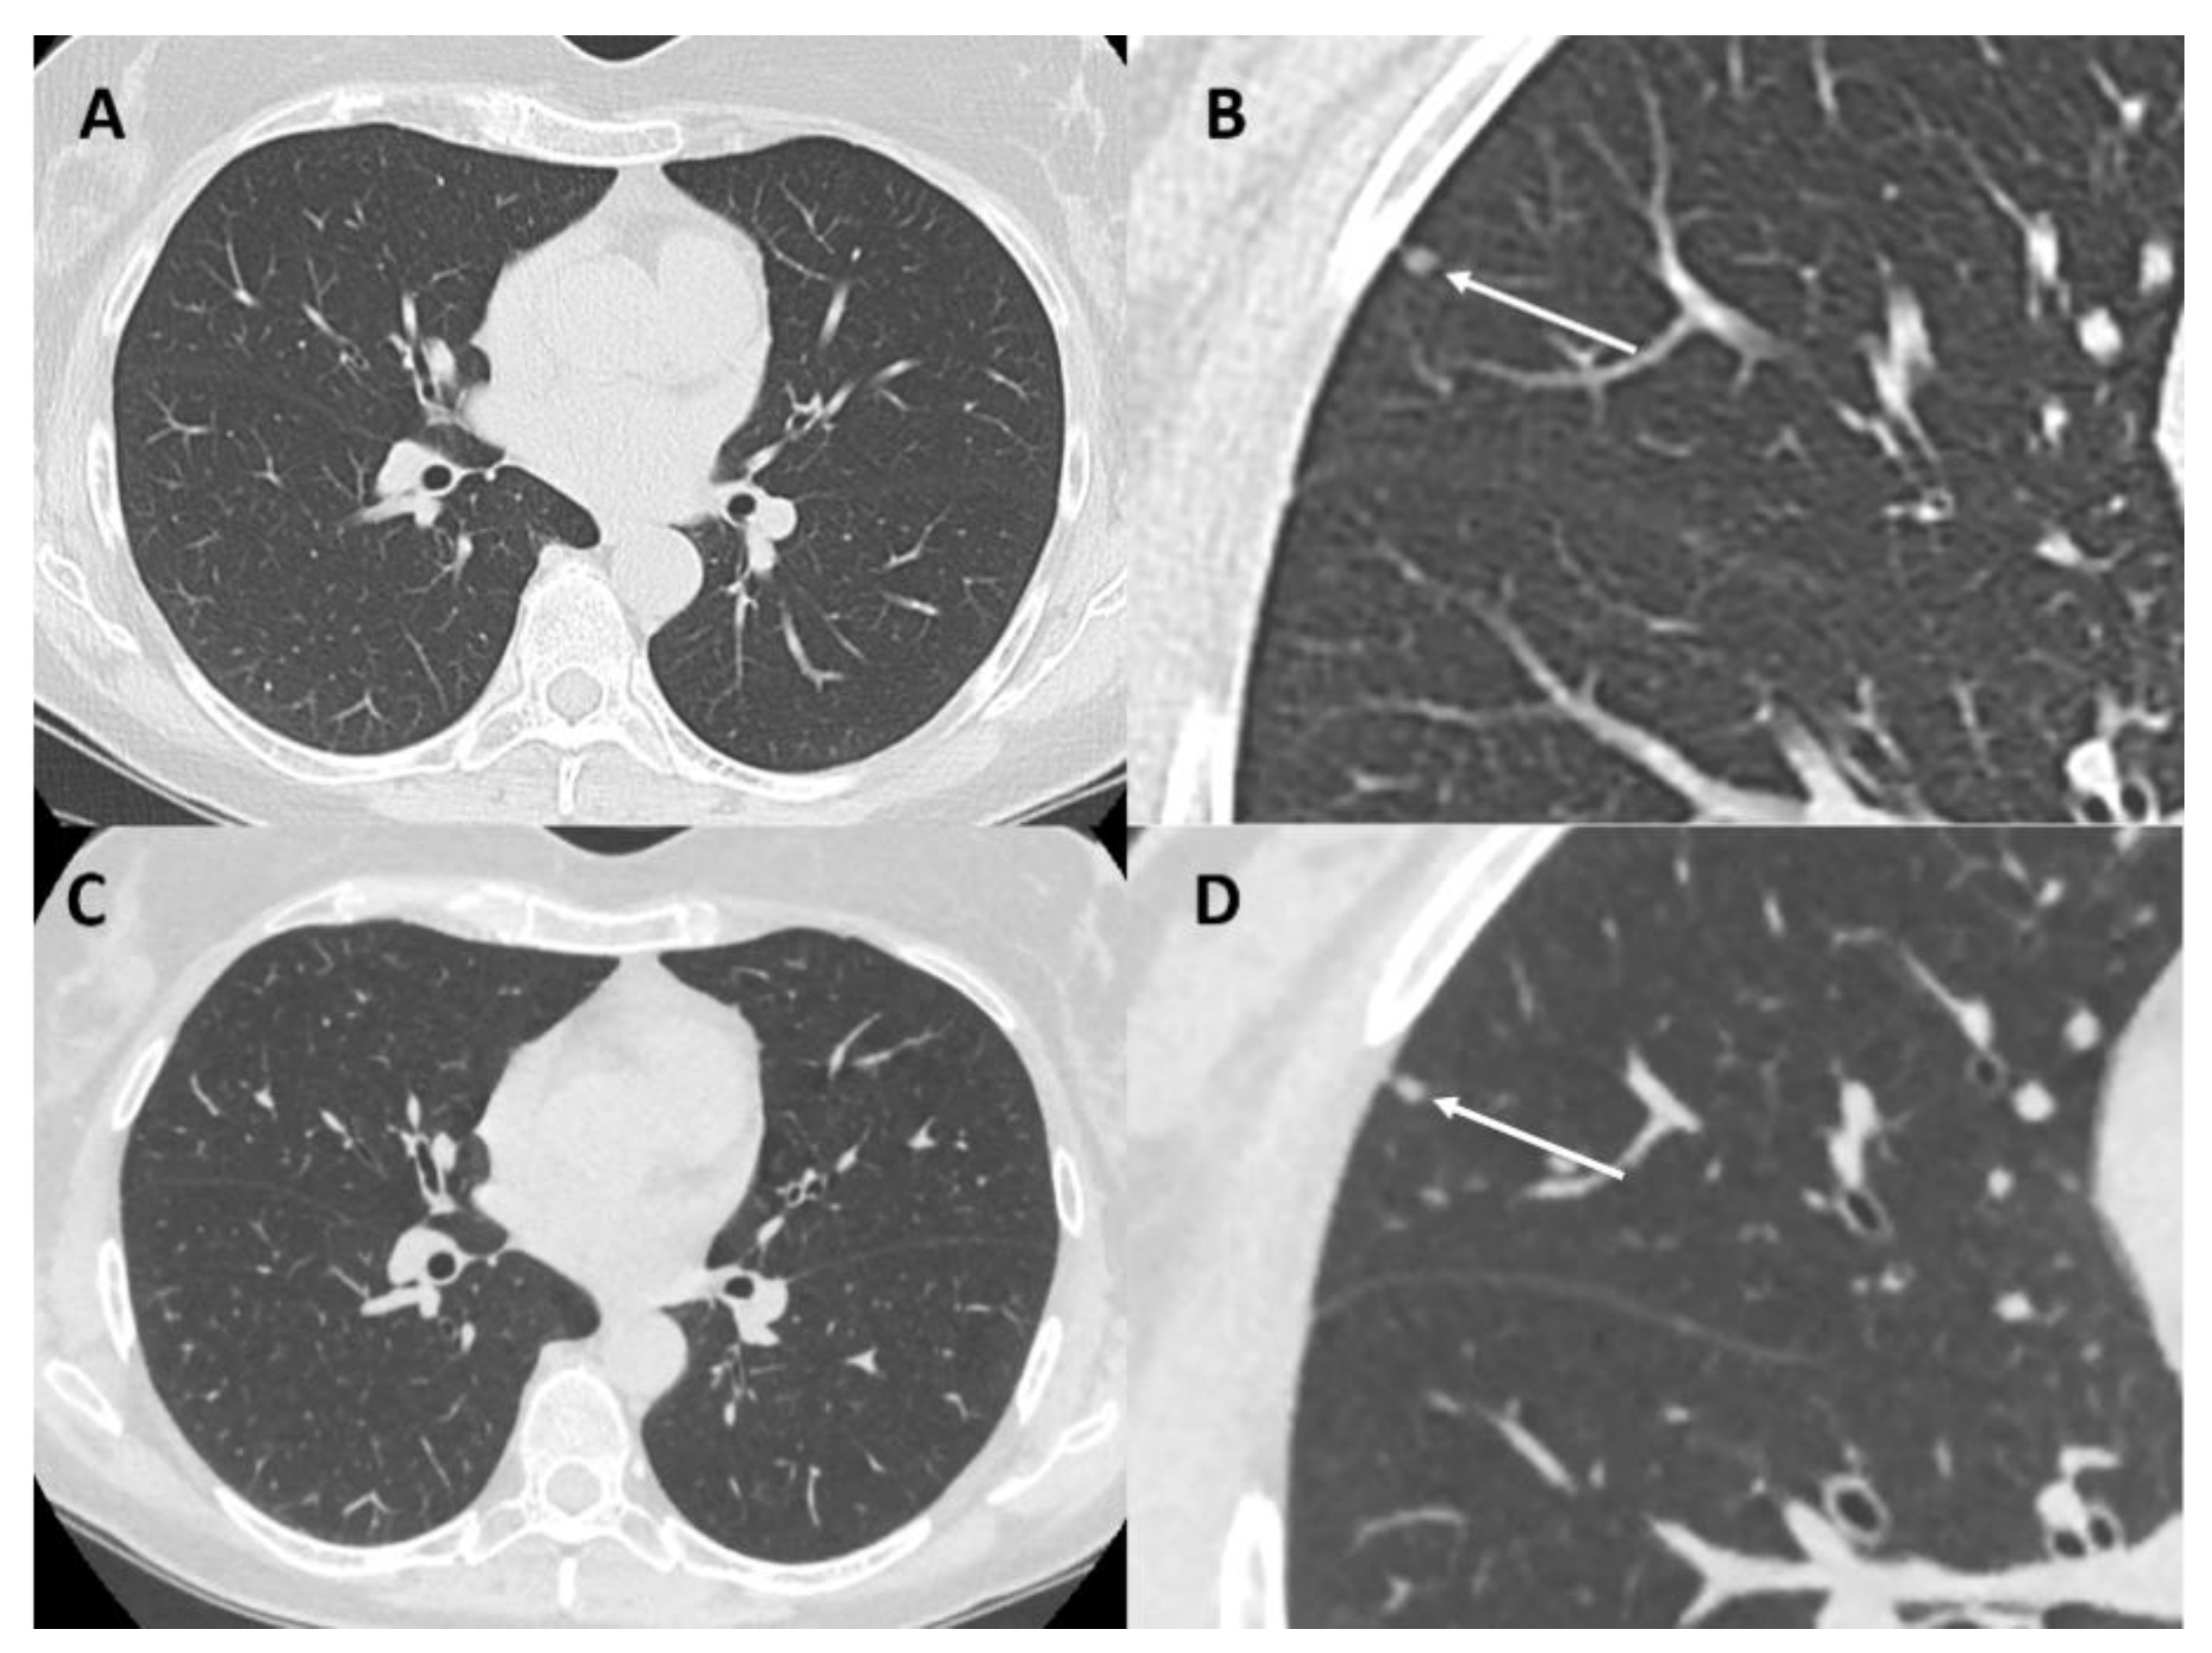

3.1. Typical and Atypical Manifestation of Lung Metastases

- Ciccarese, F.; Bazzocchi, A.; Ciminari, R.; Righi, A.; Rocca, M.; Rimondi, E.; Picci, P.; Reggiani, M.L.B.; Albisinni, U.; Zompatori, M.; et al. The many faces of pulmonary metastases of osteosarcoma: Retrospective study on 283 lesions submitted to surgery. Eur. J. Radiol. 2015, 84, 2679–2685. [Google Scholar] [CrossRef]